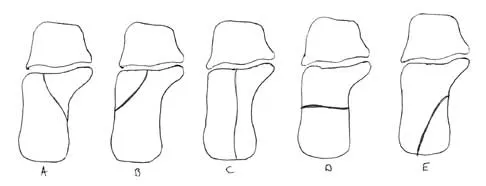

A 23-year-old man who was the restrained driver in a car involved in a high-speed motor vehicle accident sustained the closed injury shown in Figures 32a through 32c. Which of the following factors has the greatest impact on the risk of osteonecrosis?

Explanation

The incidence of osteonecrosis following displaced talar neck fractures is most related to the extent of initial fracture displacement. With increasing fracture displacement, the tenuous vascular supply to the talar body is more at risk for damage, thereby increasing the risk of osteonecrosis. Although displaced talar neck fractures have historically been considered a surgical emergency, recent studies have shown that the timing of surgical intervention bears no impact on the development of osteonecrosis. While nicotine use has an influence on fracture healing, it has never been shown to be a factor in osteonecrosis, nor has posterior-to-anterior screw fixation or the quality of fracture reduction. Lindvall E, Haidukewych G, Dipasquale T, et al: Open reduction and stable fixation of isolated, displaced talar neck and body fractures. J Bone Joint Surg Am 2004;86:2229-2234.